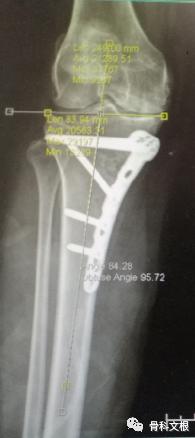

拍片结果

文根主任查看病人后,结合病人症状,查体及辅助检查。内侧间隙明显变窄,力线偏离,考虑行关节置换较早,后期需要翻修治疗,且费用较高,文根主任决定为患者行胫骨高位截骨矫形手术治疗。

术后第二天患者下地活动,诉膝关节疼痛症状较前明显改善。术后第五天患者自诉“疼痛明显减轻,膝关节活动度一天比一天好,现在可自己下蹲”表示对手术效果非常满意!